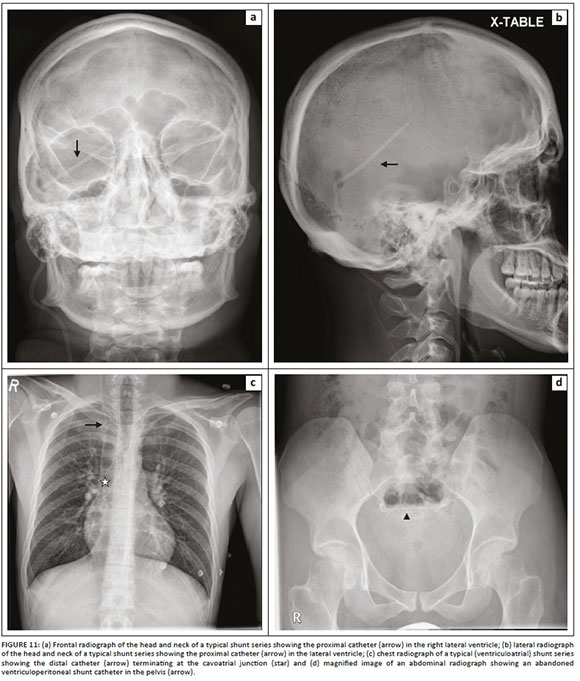

Medical devices and materials such as electrocardiogram (ECG) leads, ventilator tubing, syringes, clamps, temperature sensors, post-coronary artery bypass grafting (CABG) sternotomy wires, surgical clips, orthopaedic implants, gown snaps, etc. are commonly seen on CXRs. Because of its limited scope, we have not included cardiac devices in this article. However, there are other non-cardiac iatrogenic objects that can be seen on CXRs and these have been summarised in Table 2. Radiologists need to recognise them, be aware of their function and look for any related complications.